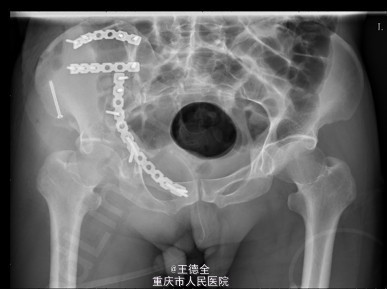

患者男性,51岁,因“高坠伤致左腰部及右髋部疼痛伴活动障碍3天”入院。急性痛苦面容,神志清楚,平车送入病房,右髋部软组织稍肿胀,局部皮肤完整,未见明显皮疹,挫擦伤及出血点.右股骨髁上骨牵引在位,左腰椎伴明显压痛,骨盆挤压实验阳性,可扪及骨擦音,骨擦感.双下肢感觉,活动,血循良好,足背动脉搏动好;右踝关节主动活动受限,被动活动正常。右侧各足趾背伸、跖屈活动正常,其余各关节活动正常。骨盆X线片示:右侧髂骨、髋臼、双侧耻骨上支、右侧耻骨下支多发骨折,左侧髂骨翼骨折,骨盆出入口右侧份形态失常。 初步诊断:右髋臼粉碎性骨折(Judet X 型) 诊疗计划:完善双下肢静脉彩超等检查;给予预防深静脉血栓、骨牵引治疗;给予止痛等对症支持治疗;密切观察病情变化,根据病情及时处理。